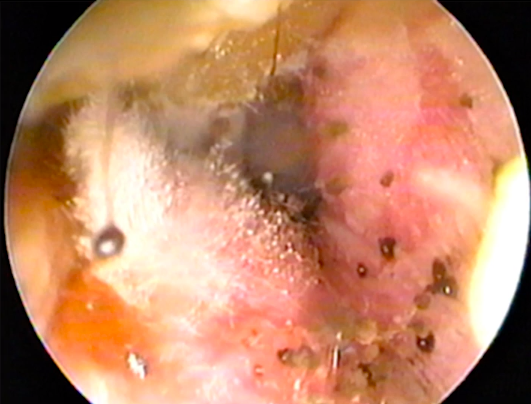

Insuficiencia nasal bilateral de meses de evolución. Consta algún episodio de asma en la infancia

A

Poliposis ( formaciones con aspecto de granos de uva habitualmente bilaterales ) . Si BL no se requiere una biopsia. La recidiva después de la cirugía es frecuente.